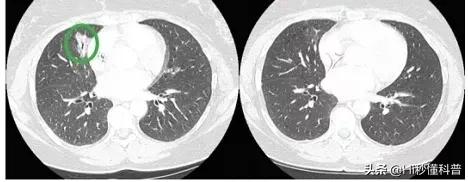

一位49岁的女士,在2012年确诊ROS1融合Ⅳ期NSCLC,她一开始使用克唑替尼治疗了5年。但是在2016年发生了新的突变,没有适合的治疗方案了。接着新一代抗癌药物瑞波替尼出现,这位女士参加了瑞波替尼的临床实验。在用药的第2个星期出现了缓解,在第6个星期100%的肿瘤全部消退。